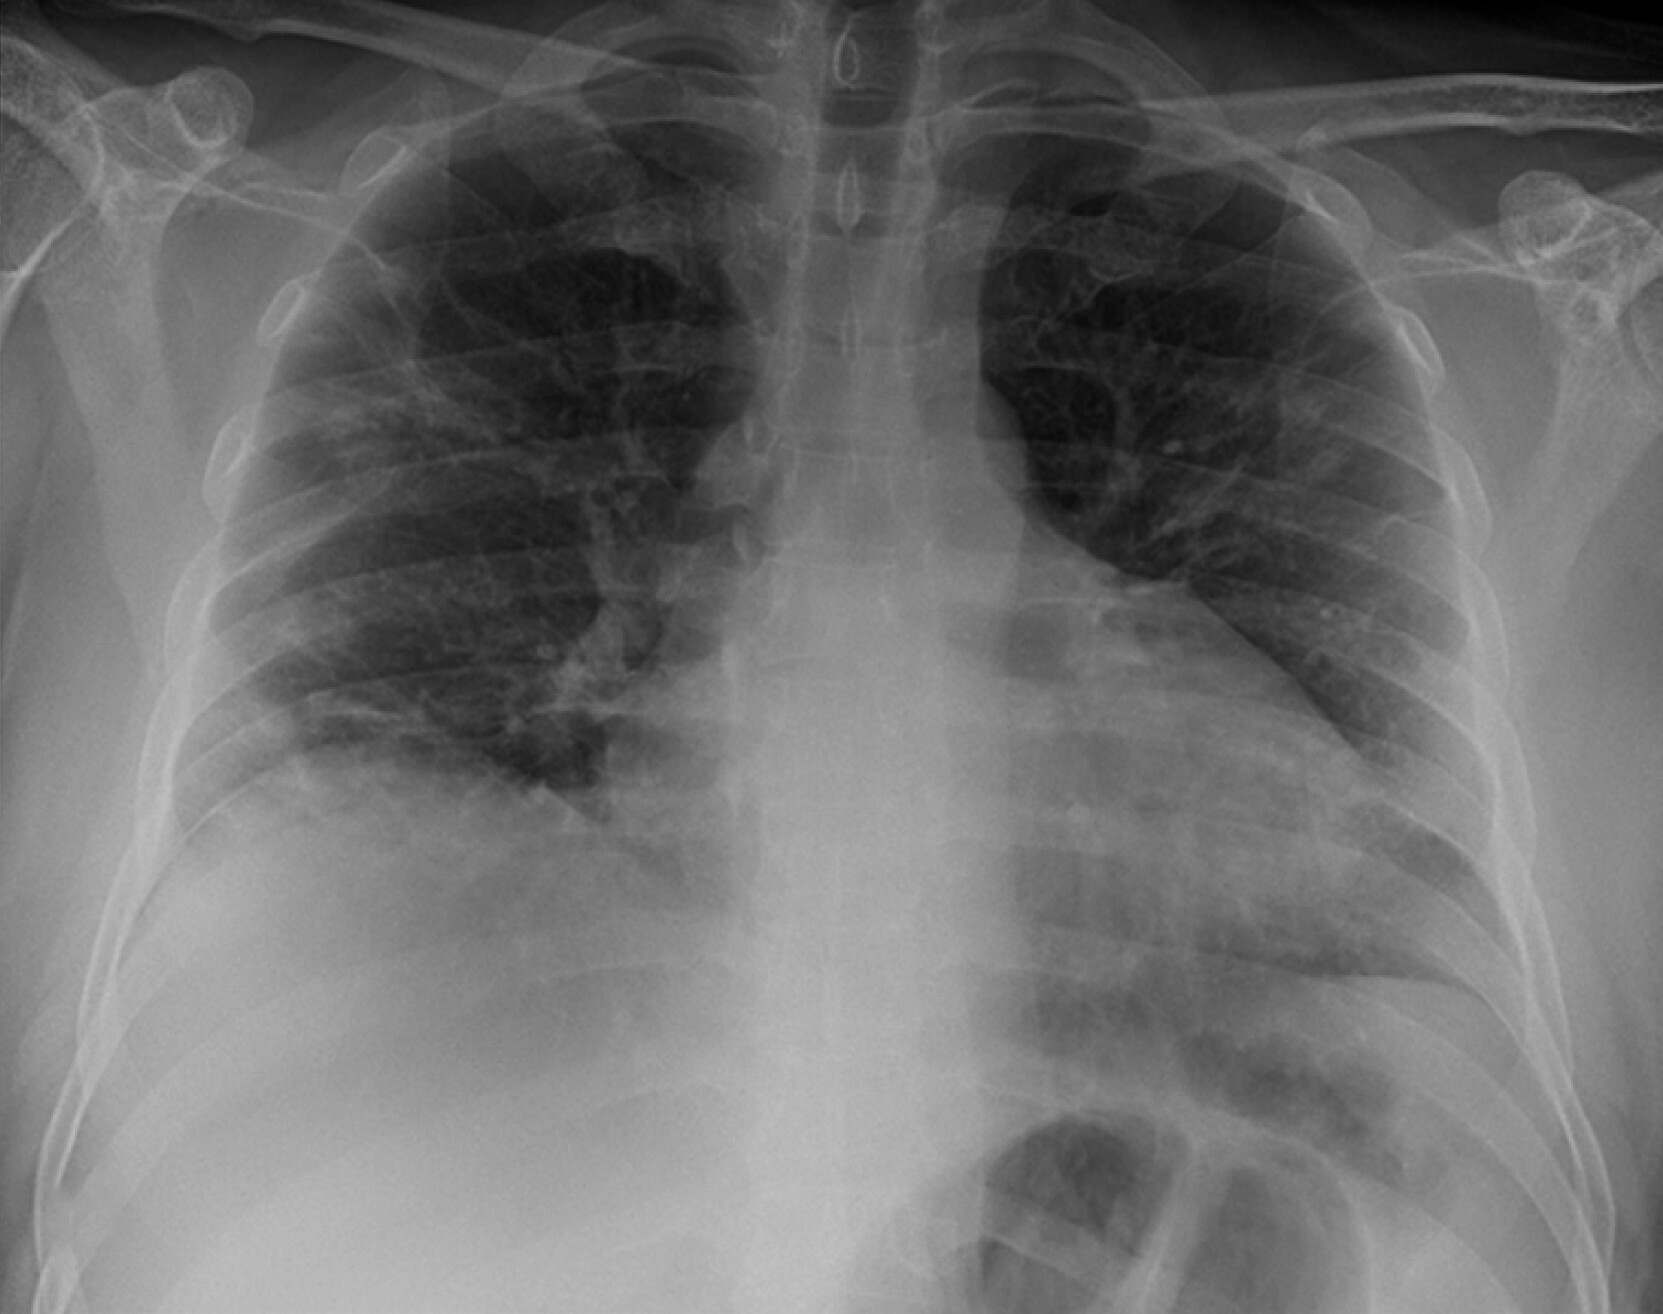

C T scans of lungs injured by C O V I D 19 and normal lungs. The Healthy lung shows clear and unmarred lung space, indicated by dark gray areas seen between the bones. The injured lung shows white clouds where the clear spaces should be indicating obstruction and damage of the airways.

TESTING At the clinic, Amber tested positive for COVID-19 caused by SARS-CoV-2, the coronavirus that emerged in 2019 and is now endemic (regularly occurring worldwide). Amber’s lung X-ray revealed fluid buildup and airway damage. Alarmed, Amber now requested the COVID vaccine—but the clinician explained that vaccination only prevents disease several weeks before infection. Amber received oxygen and stayed overnight at the hospital. Fortunately, her symptoms improved and she returned home.